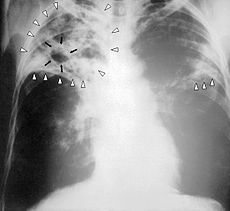

What is this?

Chest X-ray of a person with advanced tuberculosis: Infection in both lungs is marked by white arrow-heads, and the formation of a cavity is marked by black arrows.